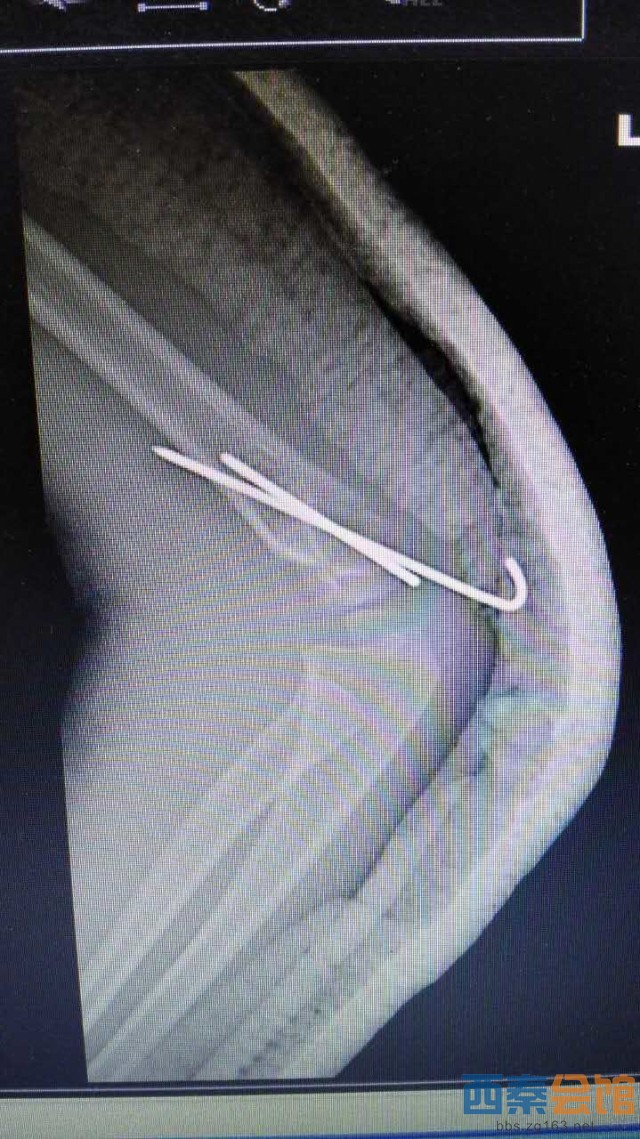

肱骨髁上骨折为儿童常见病,往往需要手术治疗,常规手术为做肘关节内外侧切口,交叉克氏针固定,手术创伤大,伤口瘢痕长,不美观等问题。市三医院骨一科梁涛主任根据患者需求,新引进儿童肱骨髁上骨折前路手术,仅3cm小切口切开复位后,于肱骨内外髁闭合穿针内固定,伤口皮内缝合,不需要拆线,术后伤口愈合快,术后4周可去除石膏托锻炼,术后6周可拔出克氏针,具有创伤小、美观、患者护理方便等优点。目前该5岁患者恢复良好,已出院休养。